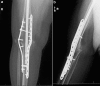

Peri-implant fracture after dual-plating knee arthrodesis for failed total knee arthroplasty: case series

Knee arthrodesis is an option in the setting of failed total knee arthroplasty. Dual-plate fixation is a described technique to obtain knee fusion in this scenario. Literature on the complications of knee arthrodesis with dual-plate constructs is limited. We present 3 cases who underwent dual-plate knee arthrodesis complicated by peri-implant femur fracture.